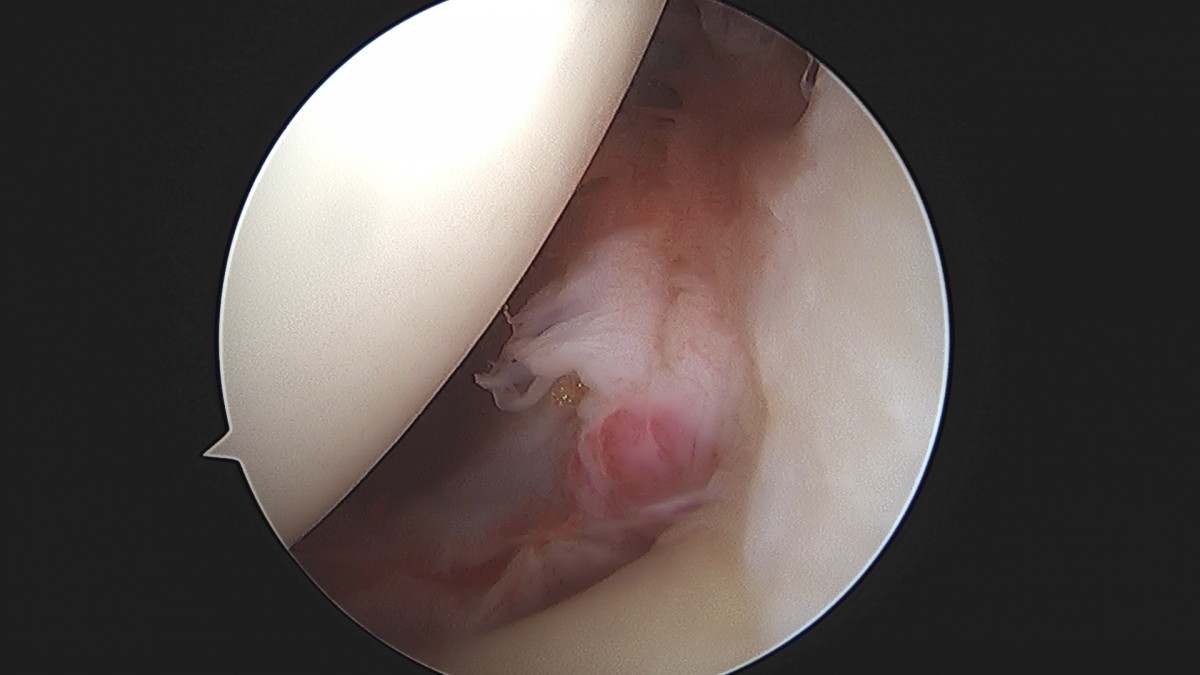

이재상원장님 어깨 견봉하 감압술 및 관절낭 이완술 주혜O 환자

dae765e4d9ac96aee867c9d6292d8784_1758003912_7954.jpg